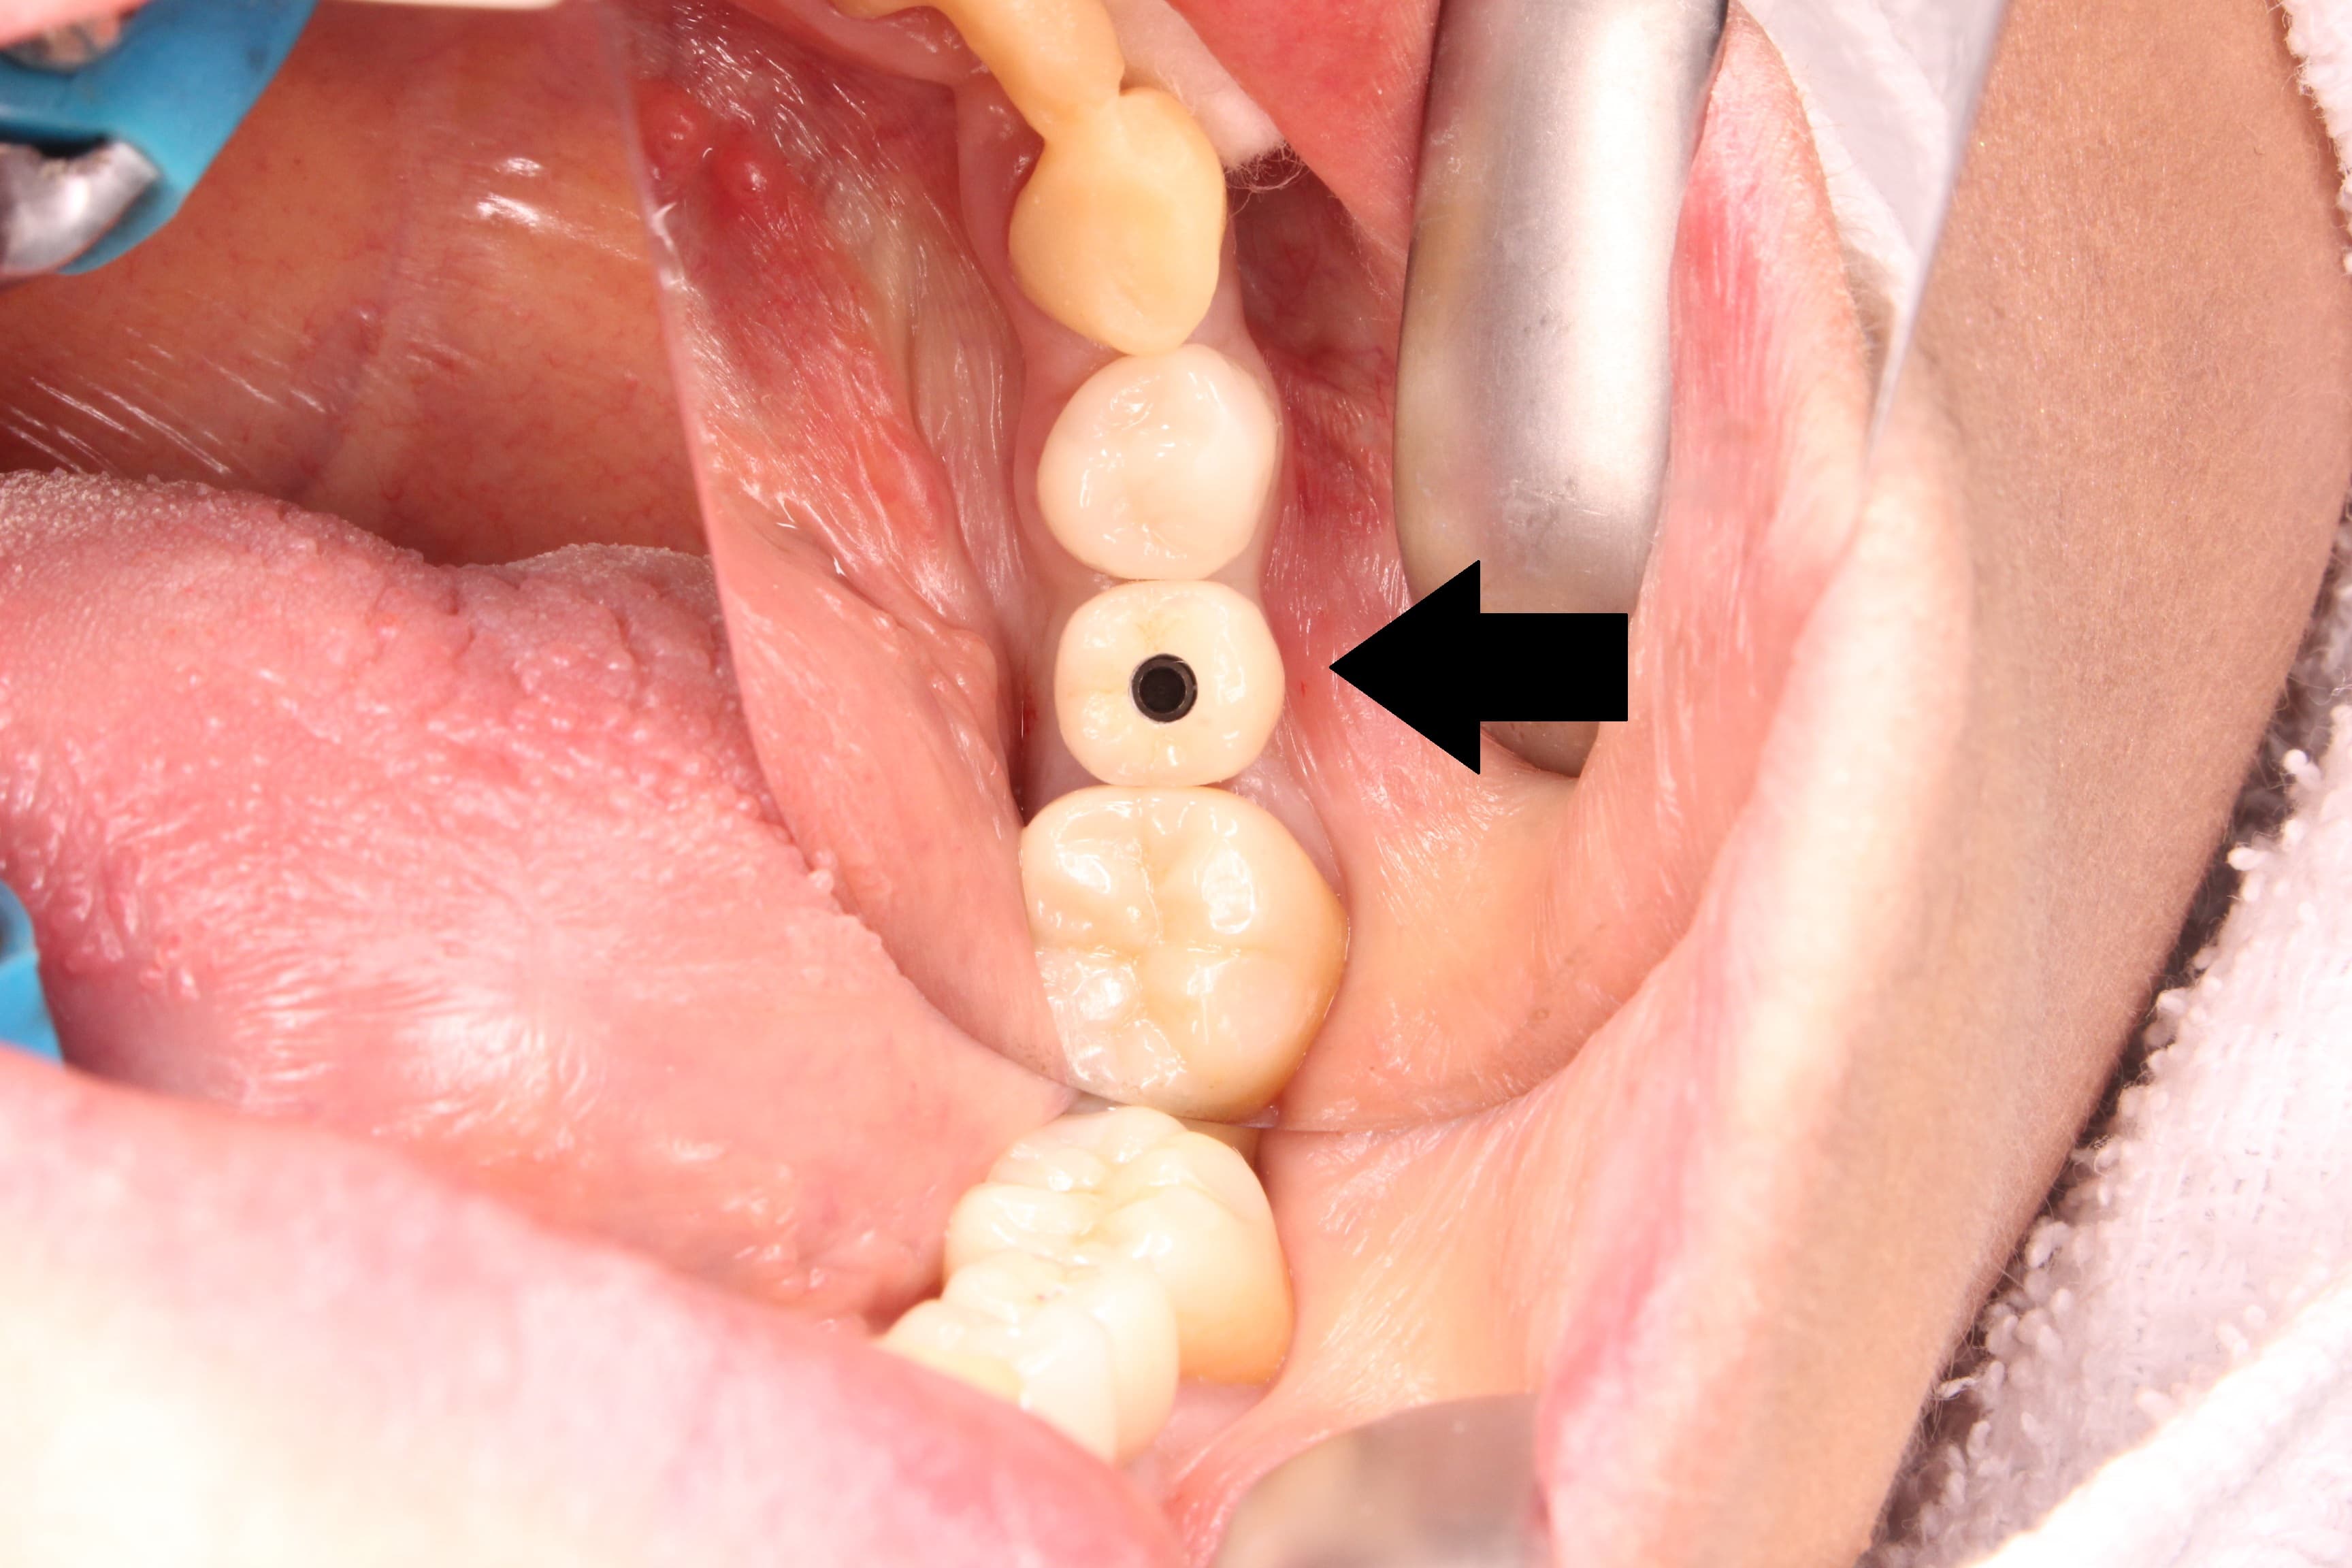

インプラント周囲の歯肉

こんにちは。 南館歯科クリニックの木村です。 インプラント症例をご紹介します。 次回インプラントの上部構造が入る予定になっています。 1次オペ、2次オペともに順調に終わり ヒーリングキャップといわれる…